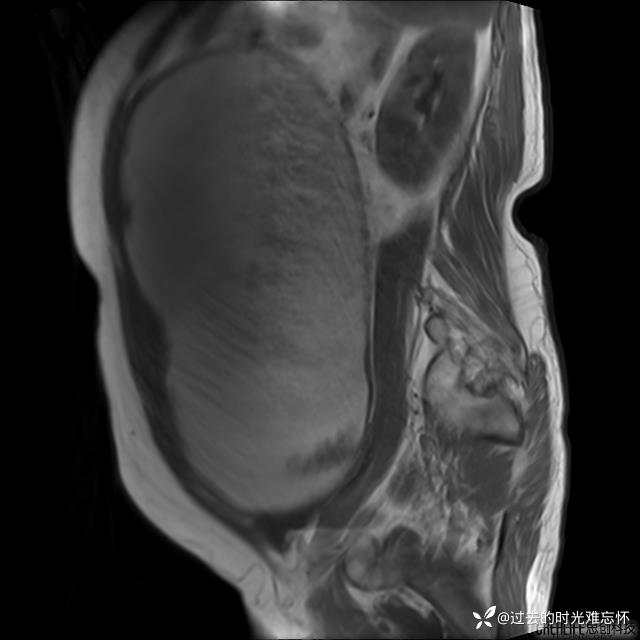

患者性别:女

患者年龄:65岁

主诉: 发现腹部隆起半年余。无其他明显不适。

浆液性囊腺瘤 (22)